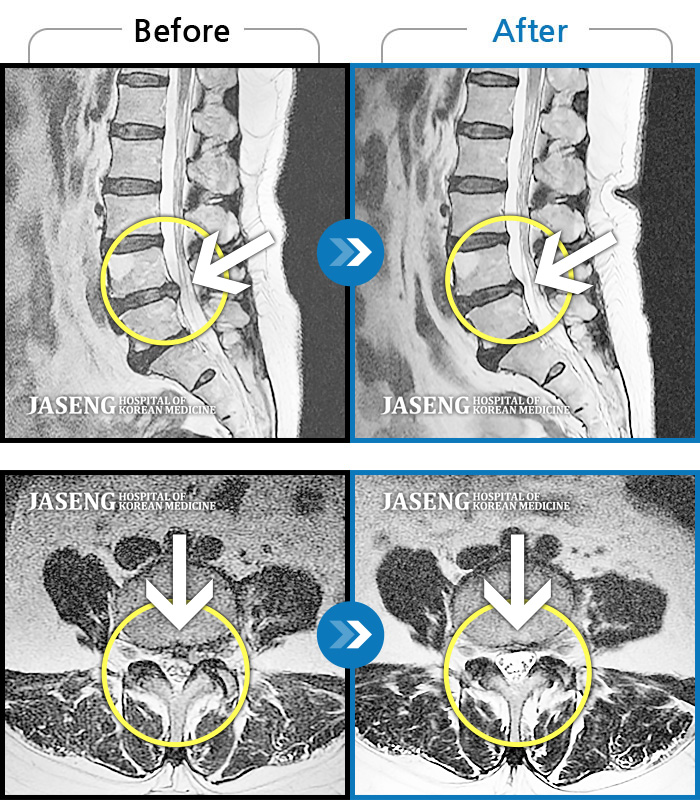

Before

After

환자에게 사전 동의를 받아 동일 조건에서 촬영되었습니다.

개인에 따라 치료 후 부작용이 발생할 수 있으니 의료진과 상담 후 치료를 진행하시기 바랍니다.

극심한 허리통증과 우측 대퇴저림으로 일상생활 불가능

아침에 일어날 때 심해지는 허리 양측 무거운 통증